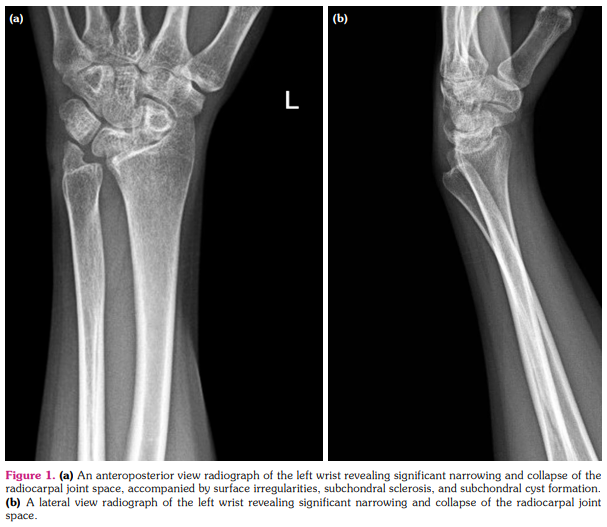

An X-ray of the left wrist (Figures 1a, b) revealed significant narrowing and collapse of the radiocarpal joint space, accompanied by surface irregularities, subchondral sclerosis, and subchondral cyst formation. No posttraumatic bone fractures were detected, and the soft tissues appeared normal. Subsequent imaging with MRI showed a further increase in the pronounced narrowing and collapse of the radiocarpal joint space, along with bone marrow edema in the subchondral region. Osteophytes were detected, along with subchondral cystic changes. Notably, marked synovitis was observed in the radiocarpal and distal radial ulnar joints. Mild radiocarpal and ulnar deformity was present, characterized by increased radial length and an ulnar slant angle, mild distal ulnar subluxation, and hypertrophy of the ulnar styloid process, consistent with the features of Madelung's deformity (Figure 2).

Plain X-rays can detect pathognomonic findings for Madelung’s deformity (Table 1).[7] The patient presented in this case had a severe form of Madelung’s deformity. Although advanced imaging are not necessary to confirm the diagnosis, an MRI delineates three-dimensional deformity, the extent of growth plate involvement, and the presence of a Vickers ligament.[8]